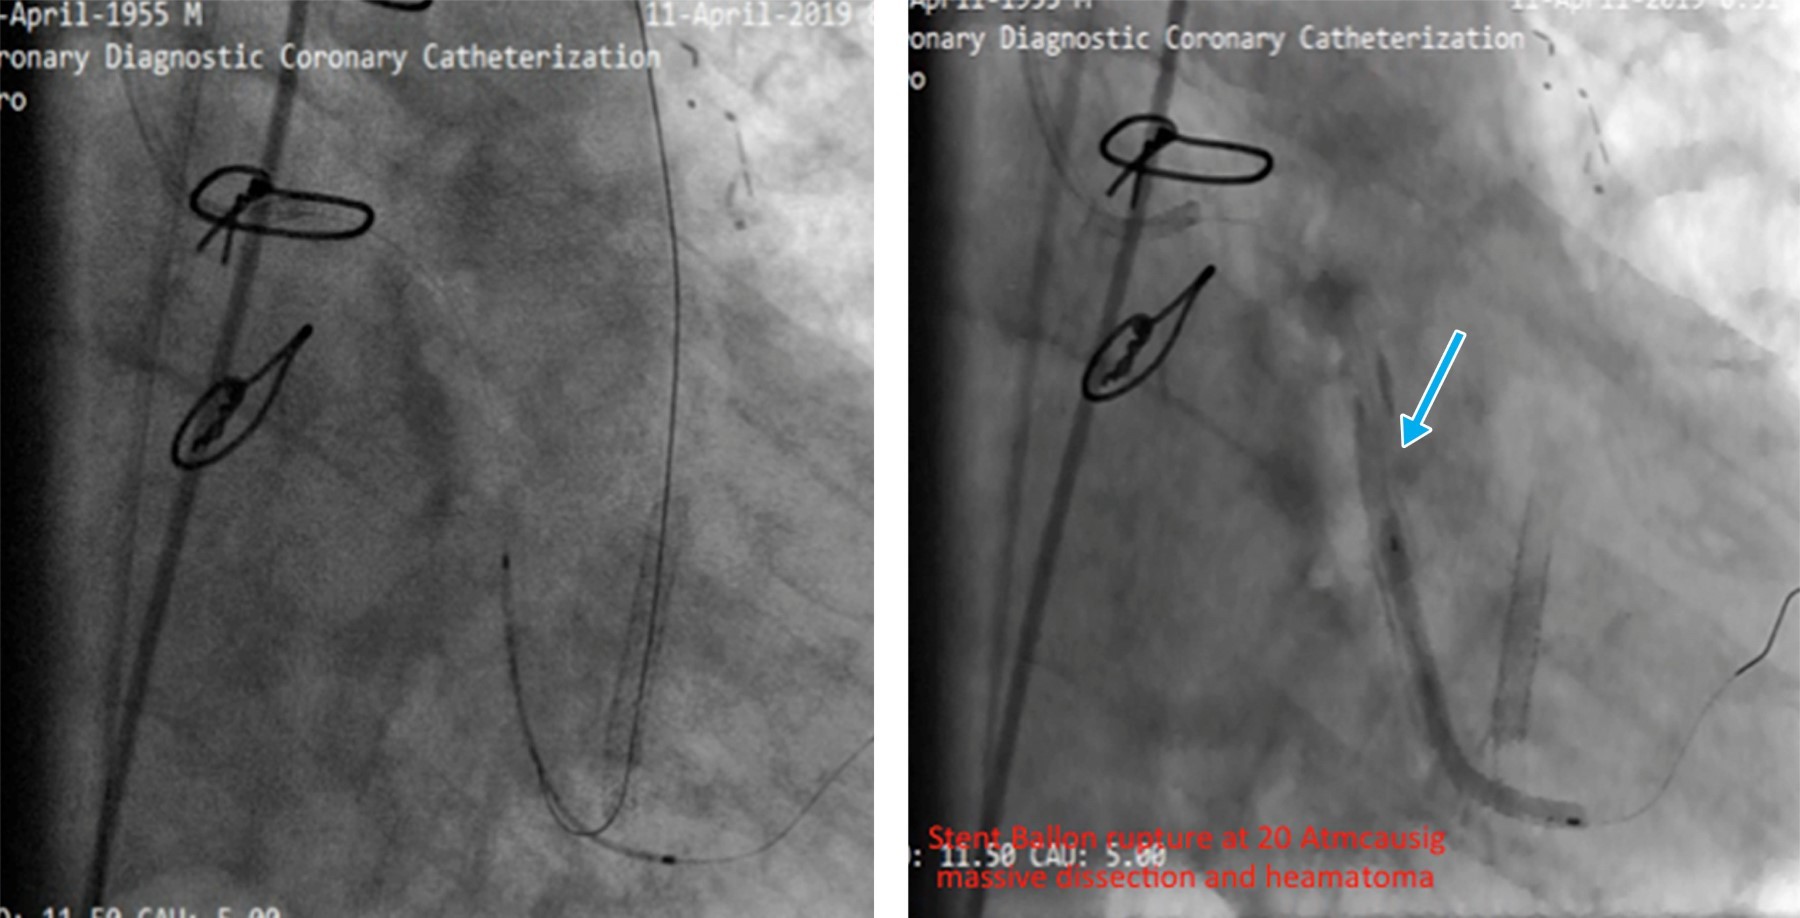

Reportamos el caso de un hombre de 78 años con antecedentes de cirugía de revascularización coronaria (CRC) e intervención coronaria percutánea (ICP) del injerto de vena safena (IVS) a la arteria marginal obtusa (MO). El paciente presentó síndrome coronario agudo y fue derivado a atención terciaria después de que la angiografía coronaria revelara reestenosis intrastent en una IVS trombótica, junto con oclusión total crónica (OTC) de la arteria circunfleja izquierda (CI). Nuestro plan inicial fue la intervención de IVS a MO debido a reestenosis del stent y trombosis. Durante el procedimiento, una rotura de balón resultó en disección y hematoma. Como intervención de rescate, se realizó stent nativo en la CI con OTC, seguido de oclusión con coil de la IVS. Surgieron complicaciones cuando el coil se desprendió y fragmentó, lo que llevó a la embolización de una partícula en la aorta descendente y la otra en la arteria femoral. Ambos fragmentos se recuperaron con éxito mediante un lazo. Este caso destaca la complejidad del manejo de las complicaciones de la ICP relacionadas con la IVS y la importancia de manipular cuidadosamente el dispositivo durante los procedimientos de colocación de la bobina.

Figura 3